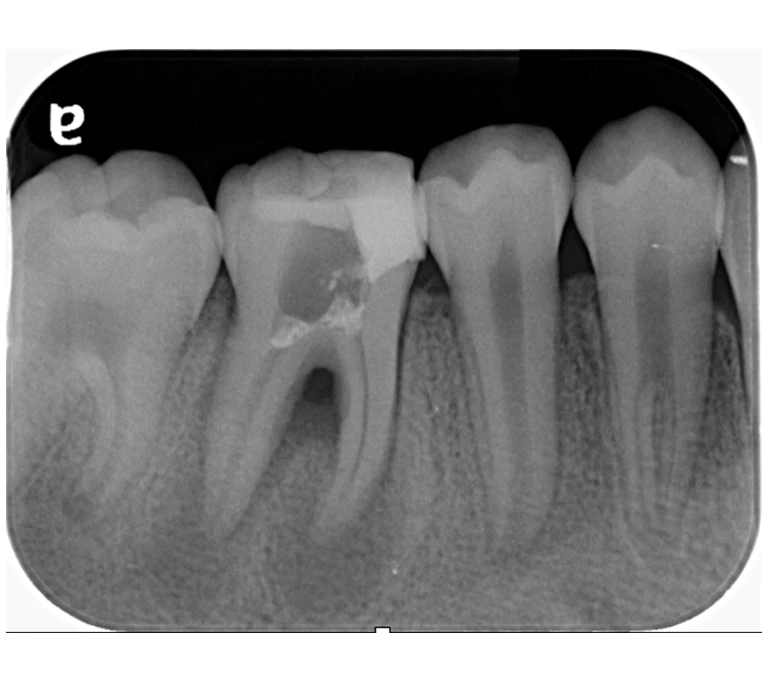

case 2.

治療前

治療後

| 主訴 | 左下歯ぐきの腫れ。 |

|---|---|

| 治療期間 | 約2か月 |

| 治療費 | 約1万5千円 |

| 治療内容 | ラバーダム、マイクロスコープ下にて根管治療を施術。 歯ぐきの腫れ、痛みや違和感が消失したため根管充填、支台築造(土台の製作)を行った。治療後の写真は矯正治療を行うことになったため仮歯を装着した状態。 |

| 治療のリスク | マイクロスコープやCTを使用し、可能な限り精密な根管治療を行っていますが、歯根の形態や病変の大きさ、過去の治療履歴などにより、治癒が得られない場合があります。また、治療後に再感染や歯根破折が生じることもあり、その場合は再治療や抜歯が必要となることがあります。 治療結果には個人差があり、すべての症例で同様の経過を保証するものではありません。 |